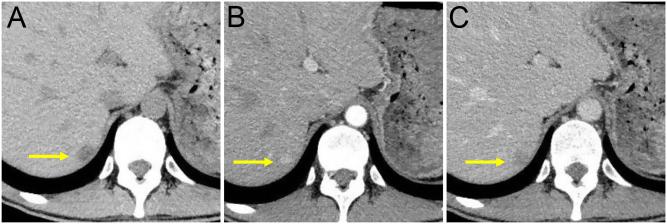

A 31-year-old man with Williams syndrome (WS) was referred to our hospital because of a 9-year history of hypertension, hypokalemia, and high plasma aldosterone concentration to renin activity ratio. A diagnosis of primary aldosteronism (PA) was clinically confirmed but an abdominal CT scan showed no abnormal findings in his adrenal glands. However, a 13-mm hypervascular tumor in the posterosuperior segment of the right hepatic lobe was detected. Adrenal venous sampling (AVS) subsequently revealed the presence of an extended tributary of the right adrenal vein to the liver surrounding the tumor. Segmental AVS further demonstrated a high plasma aldosterone concentration (PAC) in the right superior tributary vein draining the tumor. Laparoscopic partial hepatectomy was performed. The resected tumor histologically separated from the liver was composed of clear cells, immunohistochemically positive for aldesterone synthase (CYP11B2), and subsequently diagnosed as aldosterone-producing adrenal adenoma. After surgery, his blood pressure, serum potassium level, plasma renin activity and PAC were normalized. To the best of our knowledge, this is the first report of WS associated with PA. WS harbors a high prevalence of hypertension and therefore PA should be considered when managing the patients with WS and hypertension. In this case, the CT findings alone could not differentiate the adrenal rest tumor. Our case, therefore, highlights the usefulness of segmental AVS to distinguish adrenal tumors from hepatic adrenal rest tumors.

一名31岁患有威廉姆斯综合征(WS)的男性因9年的高血压、低钾血症及高血浆醛固酮浓度与肾素活性比值被转诊至我院。临床确诊为原发性醛固酮增多症(PA),但腹部CT扫描显示其肾上腺无异常发现。然而,在右肝叶后上段发现一个13毫米的高血管性肿瘤。随后肾上腺静脉采样(AVS)显示右肾上腺静脉有一条延伸至肿瘤周围肝脏的分支。分段AVS进一步证实引流肿瘤的右上分支静脉中血浆醛固酮浓度(PAC)较高。遂行腹腔镜肝部分切除术。切除的肿瘤在组织学上与肝脏分离,由透明细胞组成,醛固酮合酶(CYP11B2)免疫组化呈阳性,随后被诊断为分泌醛固酮的肾上腺腺瘤。术后,他的血压、血钾水平、血浆肾素活性和PAC均恢复正常。据我们所知,这是首例与PA相关的WS报告。WS患者高血压患病率高,因此在管理患有WS和高血压的患者时应考虑PA。在本病例中,仅CT表现无法鉴别肾上腺残余肿瘤。因此我们的病例突出了分段AVS在区分肾上腺肿瘤与肝肾上腺残余肿瘤方面的有用性。